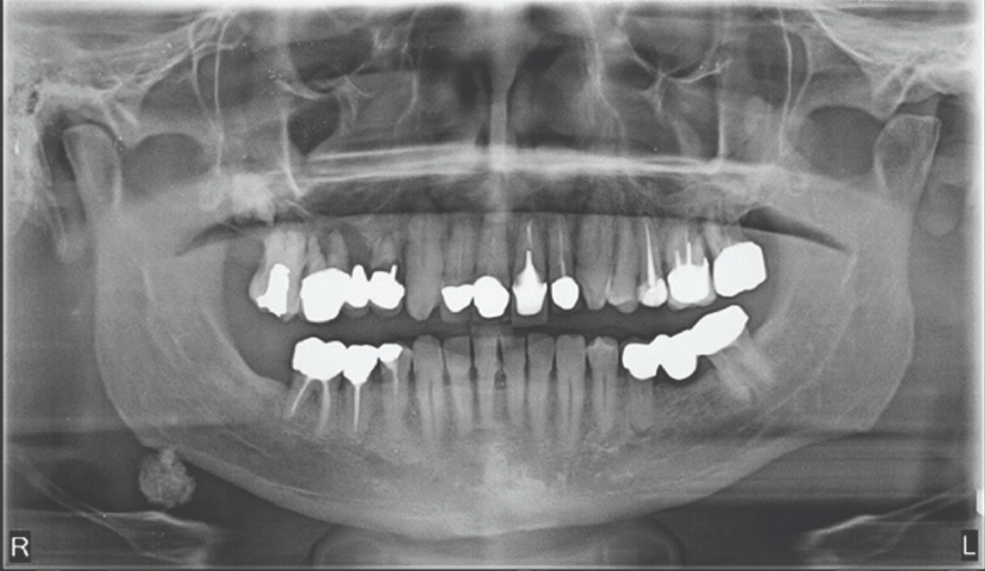

3. What condition can be seen in the following X ray?